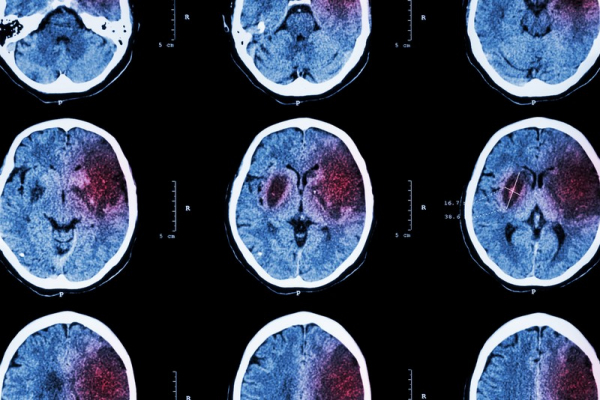

Повышенная вязкость крови — это очень опасно. В таком состоянии кровь не может полноценно выполнять свою основную функцию — транспортную. А это значит, что органы не получают необходимое количество питательных веществ и не все продукты распада будут выведены из организма. К тому же сердцу нужно тратить в разы больше энергии для того, чтобы проталкивать кровь, поэтому оно быстрее изнашивается. Из этого и вытекают инфаркты, инсульты и прочие неприятные болячки.